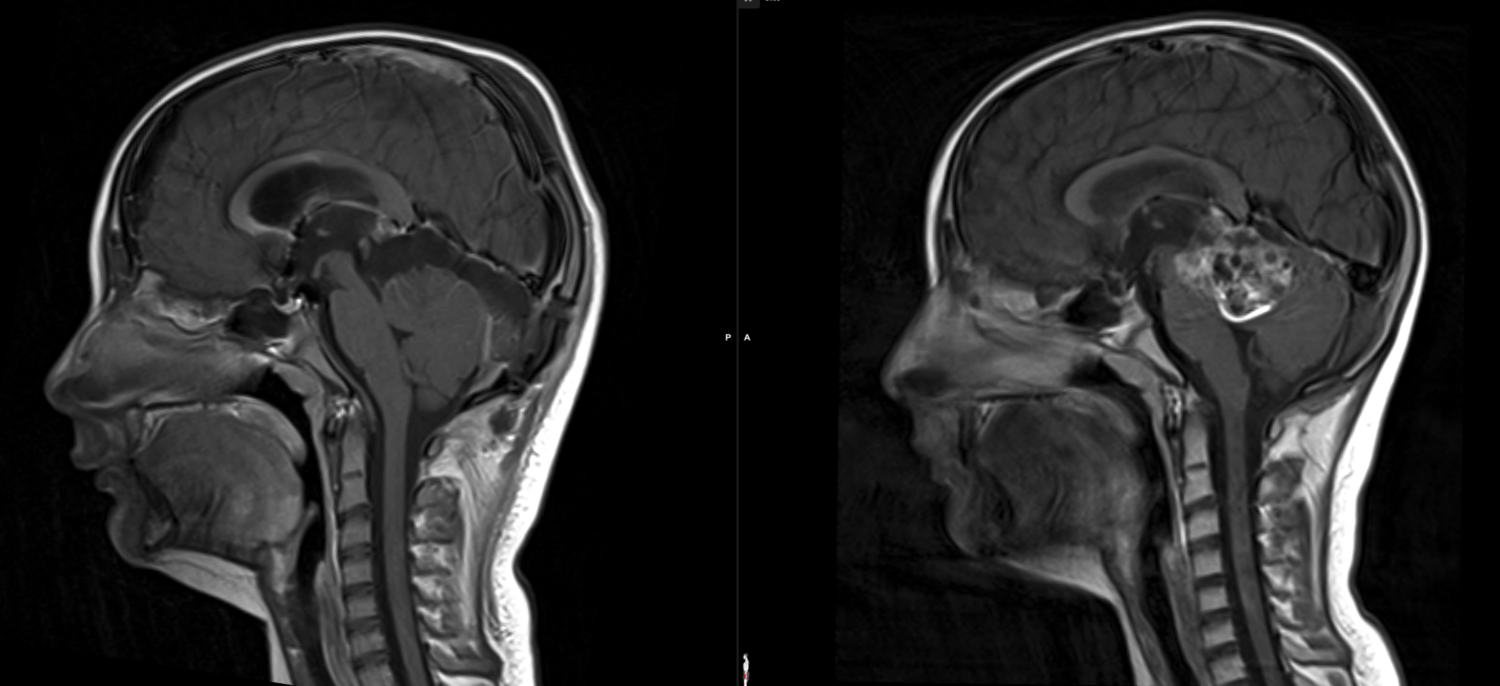

Μία απίστευτη ιστορία αποκαλύφθηκε στη Ρωσία καθώς μια 80χρονη γυναίκα έχει περάσει όλη τη ζωή της με μια βελόνα μήκους τριών εκατοστών στον εγκέφαλό της, δίχως να το γνωρίζει.

Κατά τη διάρκεια αξονικής τομογραφίας, οι γιατροί εντόπισαν τη βελόνα στον εγκέφαλο της γυναίκα σύμφωνα με τις εκτιμήσεις τους, η ηλικιωμένη υπήρξε θύμα απόπειρας βρεφοκτονίας των γονιών της, οι οποίοι τελικά αποφάσισαν να μην αφαιρέσουν τη βελόνα από τον εγκέφαλό της.

«Η βελόνα διαπέρασε τον αριστερό βρεγματικό λοβό της, αλλά δεν είχε το σχεδιασμένο αποτέλεσμα. Το κορίτσι επέζησε», σημείωσαν οι υγειονομικές αρχές, συμπληρώνοντας πως η γυναίκα δεν είχε ποτέ πρόβλημα με πονοκεφάλους, ούτε διατρέχει κάποιο κίνδυνο. Παρόλα αυτά, παρακολουθείται από γιατρό.